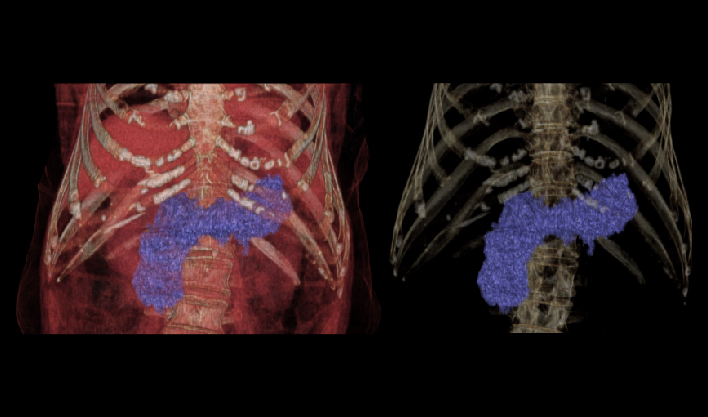

快速扫描,精准“冻结”器官运动瞬间,高清呈现亚毫米结构,为心血管等系统疾病早期诊断和治疗提供黄金窗。

百万像素成像

1024x1024重建矩阵结合薄层成像,快速锁定微小病灶(如早期肿瘤、卒中病灶),助力急诊创伤、肿瘤筛查、卒中救治的“分秒必争"。